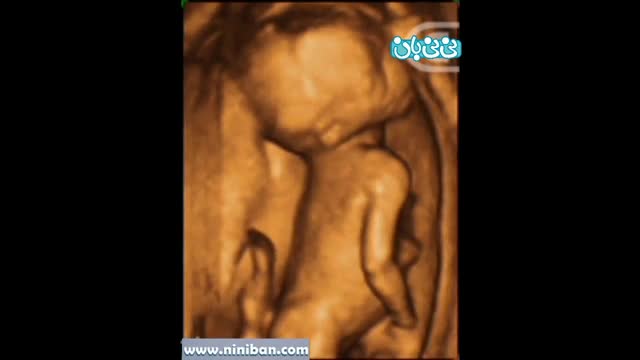

سونوگرافی چهار بعدی هفته پانزدهم بارداری

۰۰:۱۹